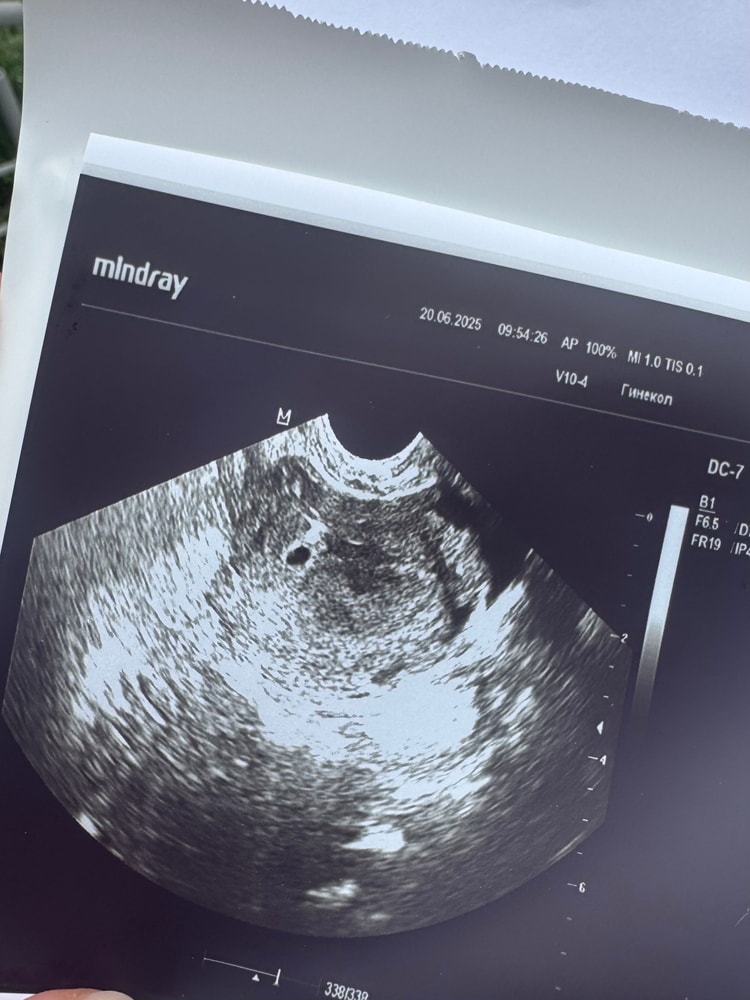

Поставили по УЗИ срок 9 недель акушерских и 8 по узи, не знаю как так уже много получилось, я думала овуляция поздняя была, так и не поняла😅

Сердечко слушали уже два раза ❤️ правда второй раз был другой аппарат и было тише слышно, теперь переживаю, надеюсь все хорошо будет